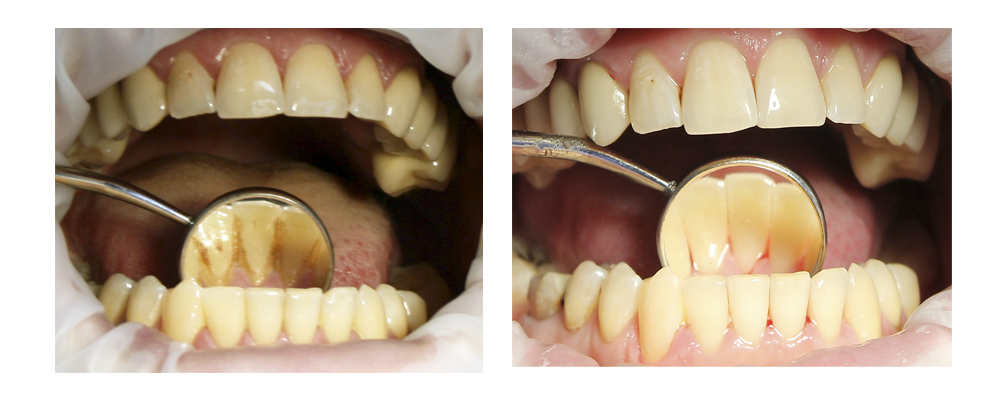

Прикорневой кариес: фото до и после

Одной из самых распространенных стоматологических болезней является прикорневой кариес, который поражает зубные ткани у корня, на границе зуба с десной, и даже может выходить за пределы коронковой части. Разрушительный процесс в этой зоне обычно развивается весьма стремительно, поскольку эмаль здесь имеет минимальную толщину: воспаление быстро проникает в глубинные слои зуба, затрагивая корневые каналы.

Как правило, прикорневой кариес встречается среди пациентов старше 30 лет, а в 60 именно это заболевание становится основной причиной потери зубов, ведь с возрастом эмаль истончается, становясь все более уязвимой. Возникновению очага инфекции способствует и сложность проведения гигиенических процедур в данной области, из-за чего около корня зуба появляется зубной камень, который благоприятствует размножению бактерий.